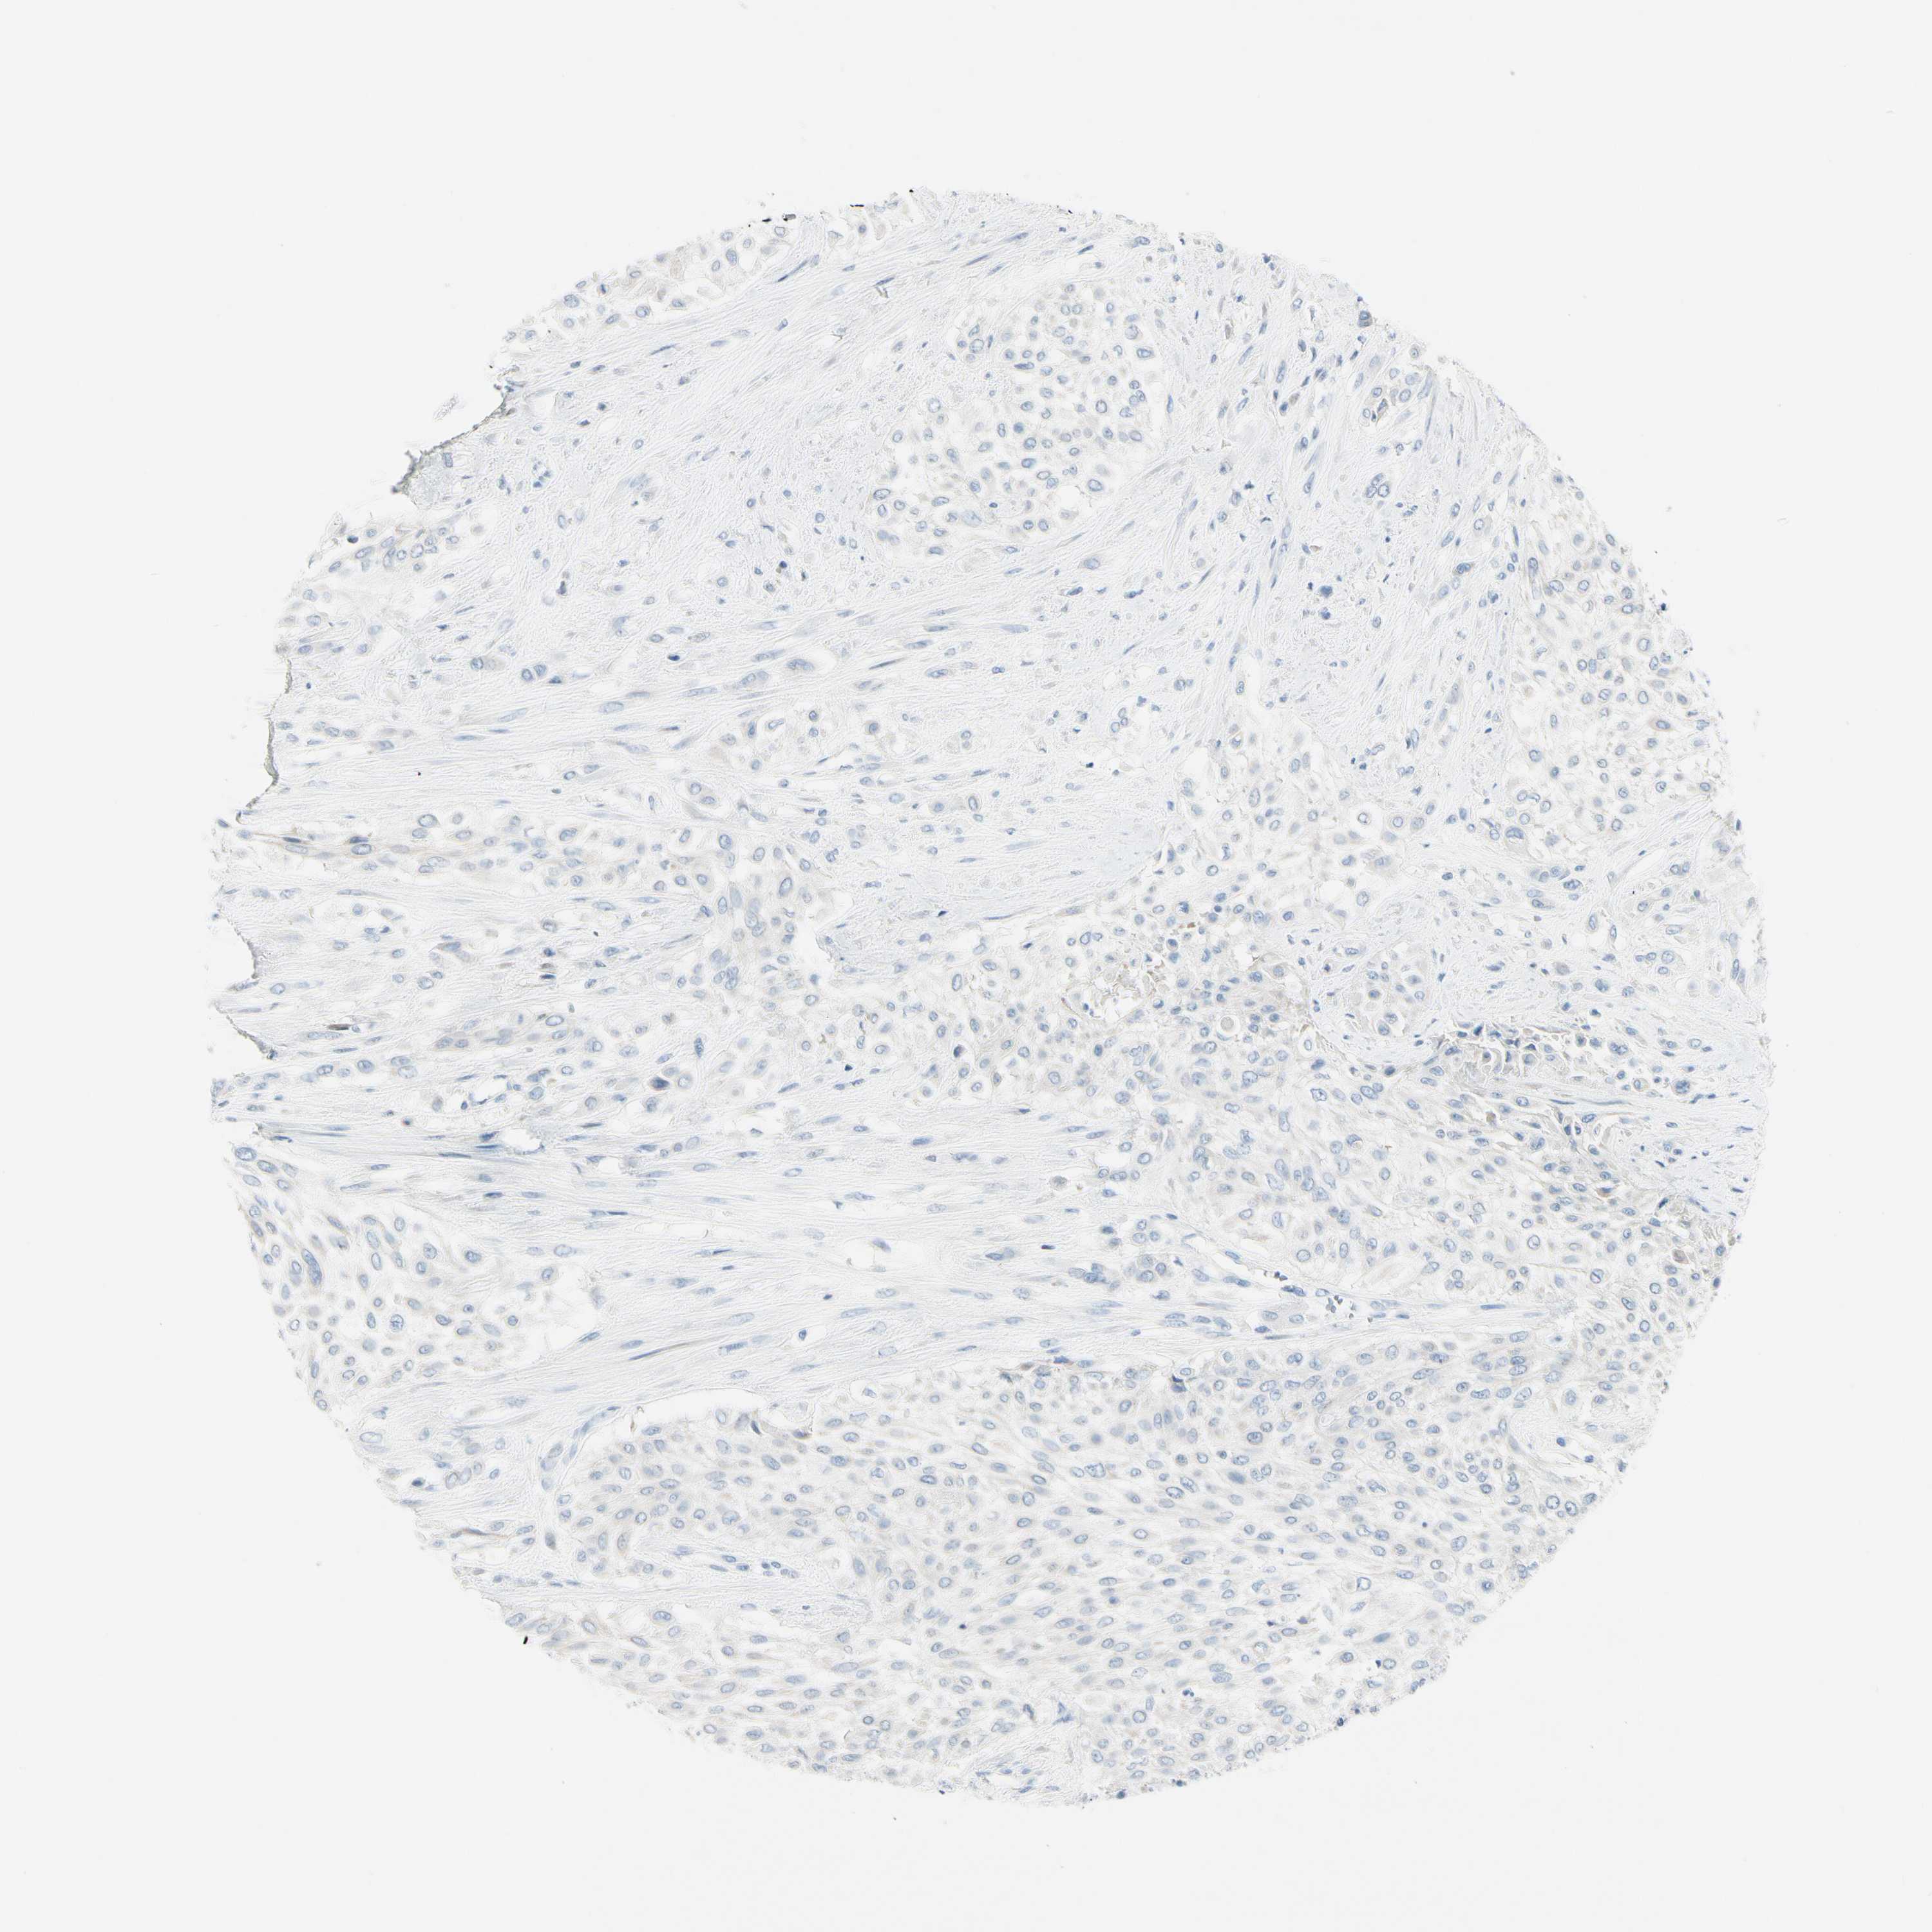

UROTHELIAL CANCER - Protein expressioni

A mouse-over function shows sample information and annotation data. Click on an image to view it in a full screen mode. Samples can be filtered based on level of antibody staining by selecting one or several of the following categories: high, medium, low and not detected. The assay and annotation is described here.

Antibody stainingi

Antibody staining in the annotated cell types in the current human tissue is reported as not detected, low, medium, or high, based on conventional immunohistochemistry profiling in selected tissues. This score is based on the combination of the staining intensity and fraction of stained cells.

Each image is clickable and will lead to virtual microscopy that enables deeper exploration of all samples and also displays staining intensity scores, fraction scores and subcellular localization as well as patient and tissue information for each sample.

Antibody HPA008819

Urothelial carcinoma, High grade

Urothelial carcinoma, Low grade

Urothelial carcinoma, NOS